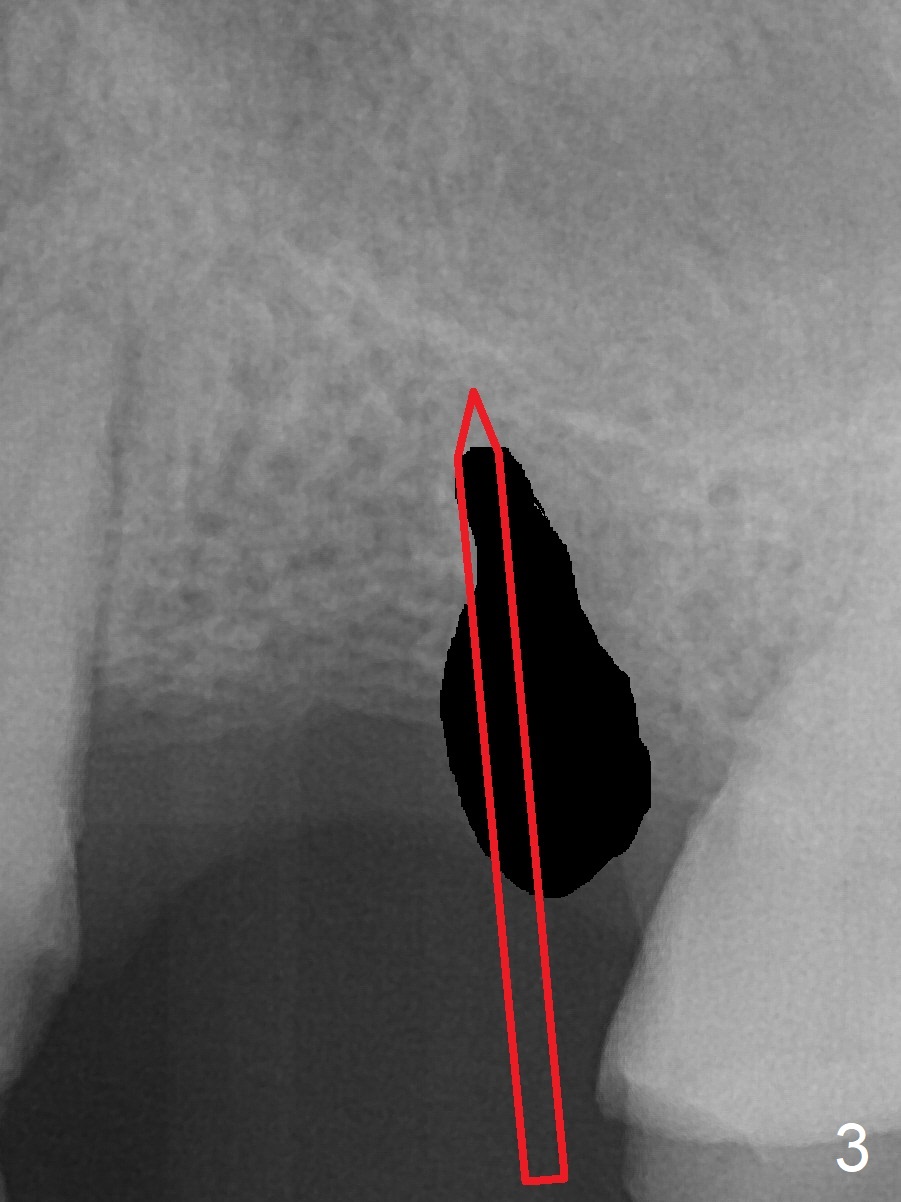

A 37-year-old man will return for #14 extraction and implant after RCT at #13 (Fig.1). After extraction (Fig.2), use Magic Expander (ME) along the long axis of the socket to initiate osteotomy shy of the sinus floor (Fig.3 (<9 mm gingival level)) and change the trajectory at the same time (Fig.4 white arrow). Take the 1st intraop PA when a small ME is stable. Gradually increase the depth for sinus lift as the diameter of MEs increases (Fig.5). Take preop photos to show the residual root and the alveolus (whether it is atrophic or not). Place bone graft (Fig.6 red circles) prior to dummy implant (green).